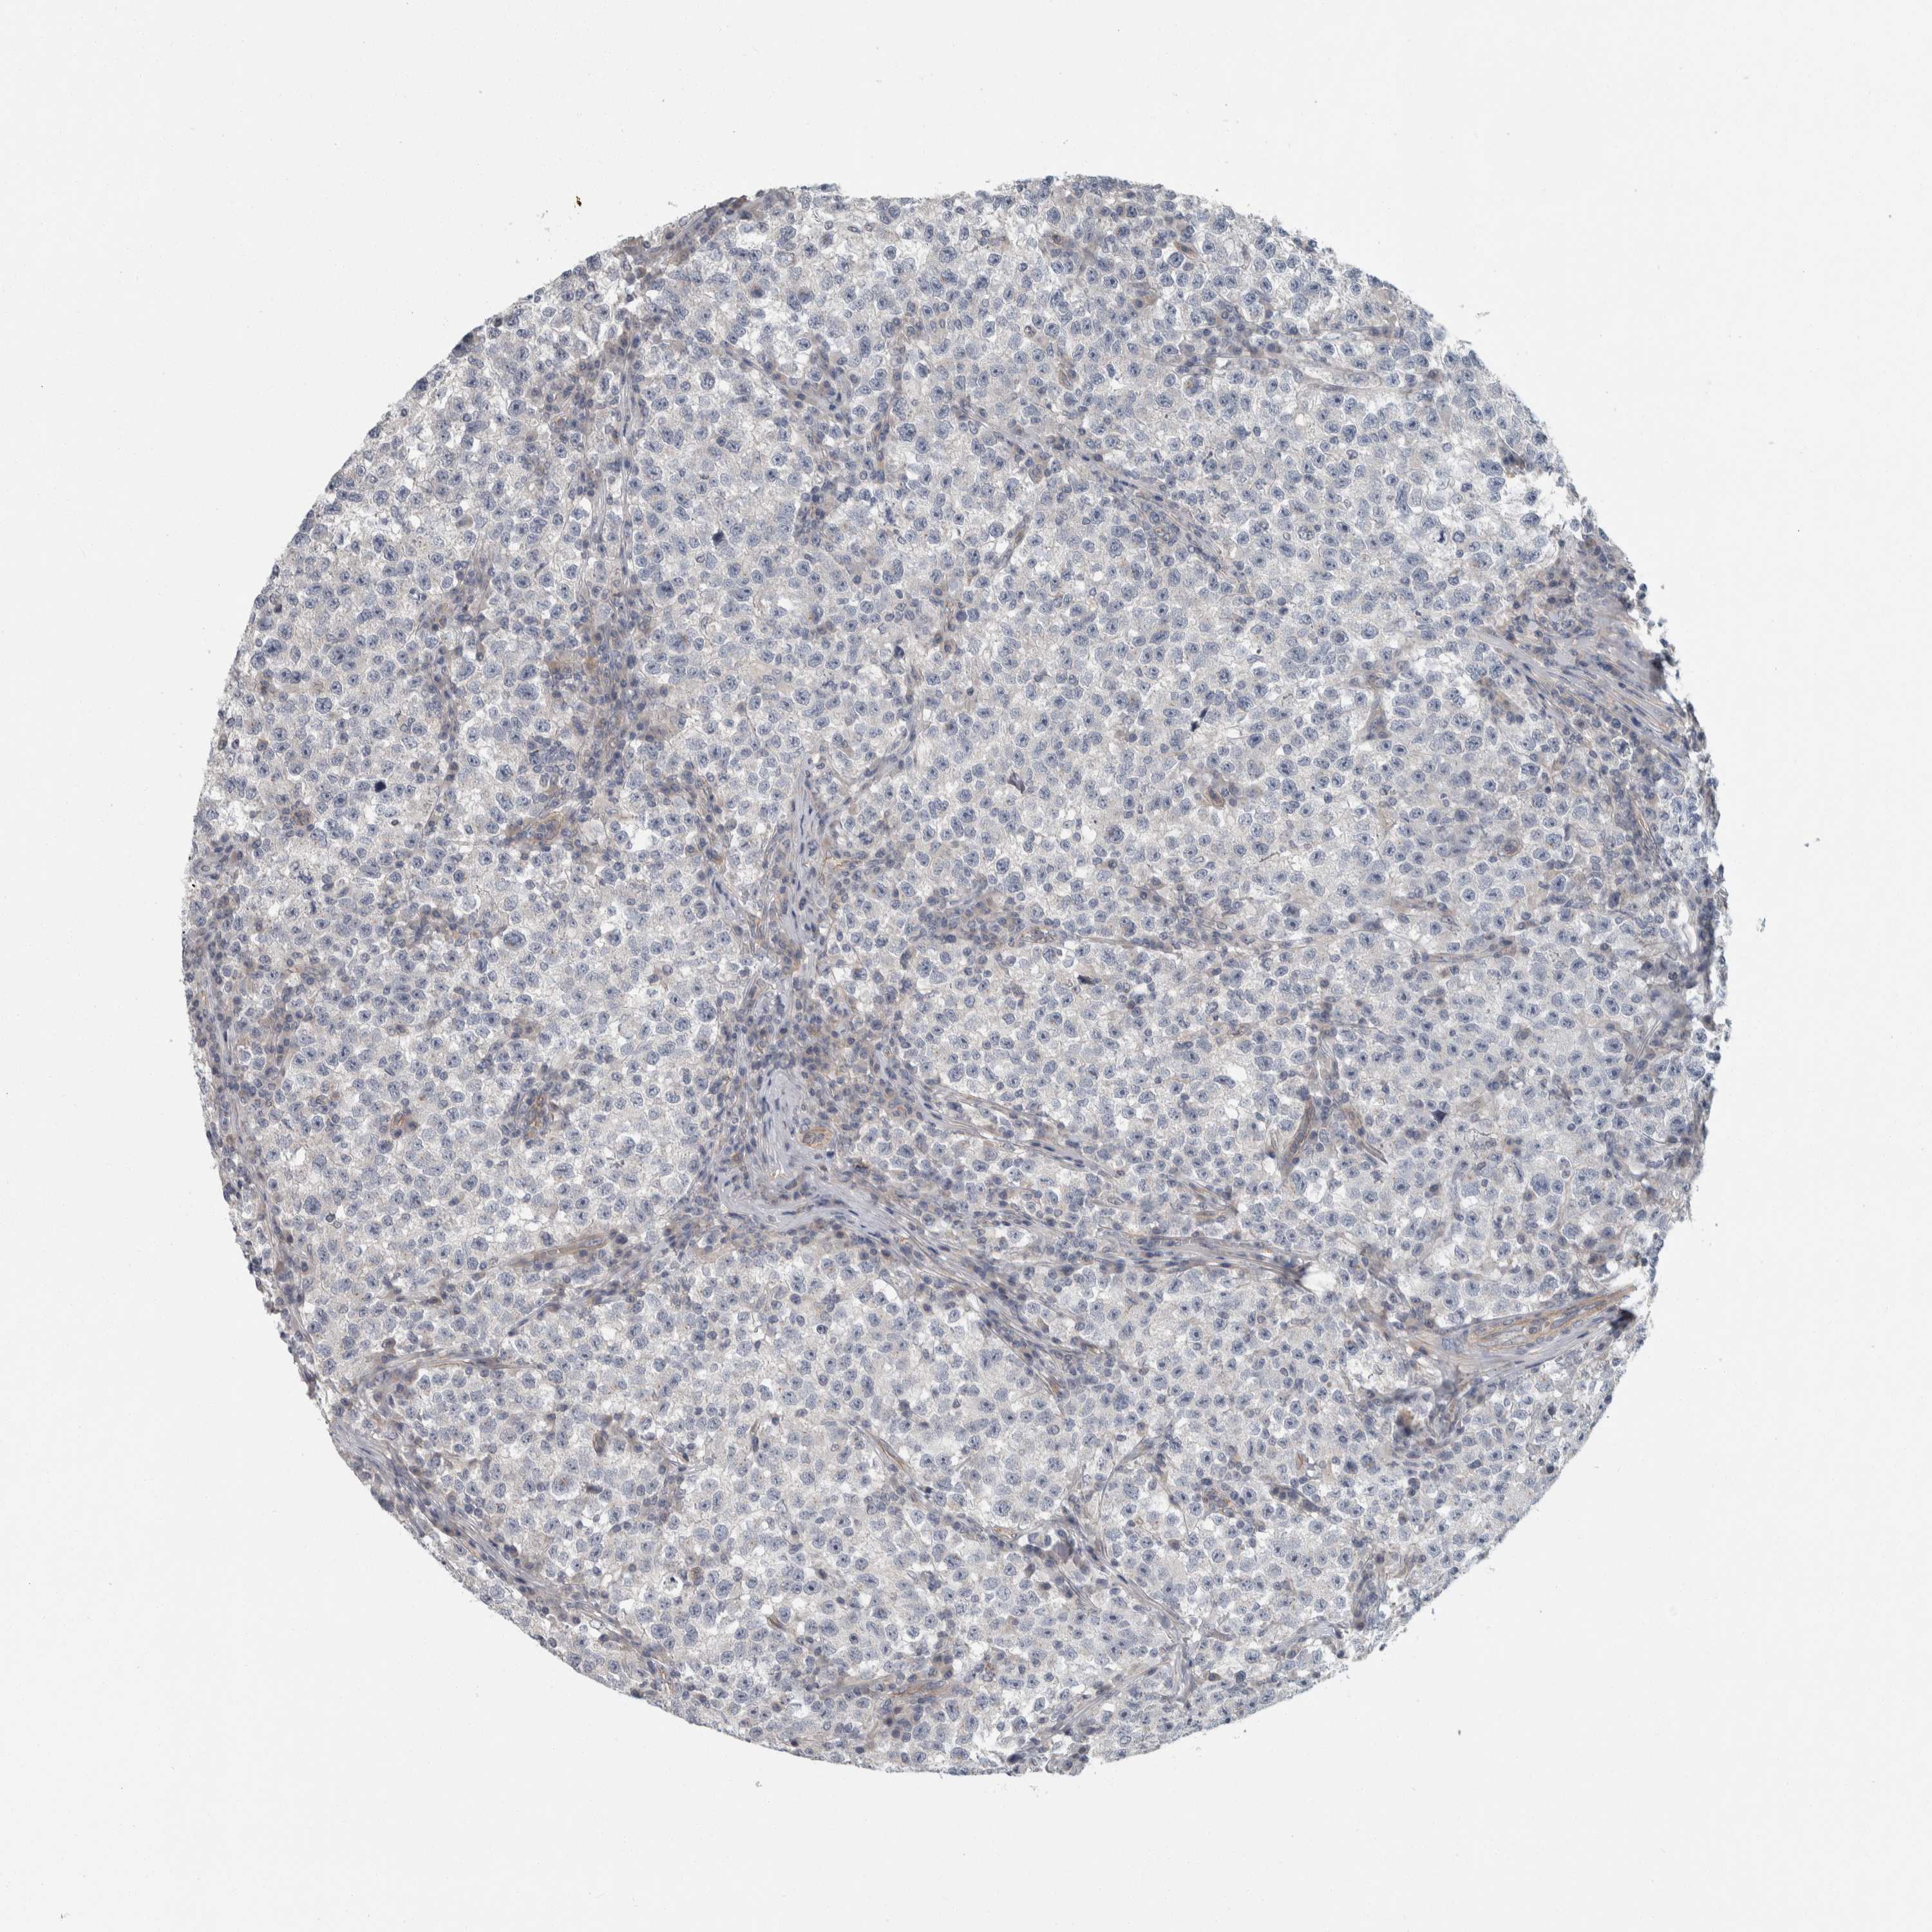

TESTIS CANCER - Protein expressioni

A mouse-over function shows sample information and annotation data. Click on an image to view it in a full screen mode. Samples can be filtered based on level of antibody staining by selecting one or several of the following categories: high, medium, low and not detected. The assay and annotation is described here.

Note that samples used for immunohistochemistry by the Human Protein Atlas do not correspond to samples in the TCGA dataset.

Antibody stainingi

Antibody staining in the annotated cell types in the current human tissue is reported as not detected, low, medium, or high, based on conventional immunohistochemistry profiling in selected tissues. This score is based on the combination of the staining intensity and fraction of stained cells.

Each image is clickable and will lead to virtual microscopy that enables deeper exploration of all samples and also displays staining intensity scores, fraction scores and subcellular localization as well as patient and tissue information for each sample.

Antibody HPA024231

Staining

High

Medium

Low

Not detected

Intensity

Strong

Moderate

Weak

Negative

Quantity

>75%

75%-25%

<25%

None

Location

Nuclear

Cytoplasmic/membranous

Cytoplasmic/membranous,nuclear

Seminoma, NOS